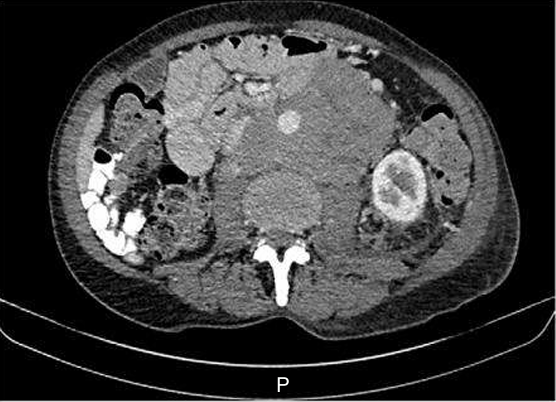

In some cases, such as those with clinical suspicion of germ cell tumours, high-grade lymphoma or small cell cancer, or those presenting with oncological emergencies, urgent referral directly to oncology or haematology is essential to allow rapid initiation of anti-cancer therapy, sometimes before investigations are completed (Fig. 1).

fig1. Young male patient presenting with a bulky midline tumour and elevated HCG and AFP suggestive of a non-seminomatous testicular cancer.